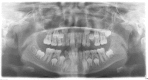

Presentation of case: A 10-year-old girl was referred to our oral and maxillofacial surgery clinic with an incidental radiological finding of radiopaque mass in the posterior region of maxilla. OPG showed unerupted tooth bud of upper right second molar and was being prevented from eruption by the odontome. Under general anaesthesia, the lesion was enucleated and the permanent right upper second molar tooth bud removed.